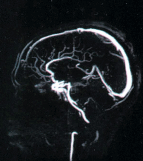

Отклонения в состоянии сосудов, которые сопутствуют ВСД и вызывают дисфункцию мозга видны при МРТ-реконструкции сосудов головы. Сопоставление сосудистых изменений с изменениями в ткани мозга помогает уточнить диагноз вегетососудистой дистонии (ВСД).

Снимки МРТ реконструкции сосудов головы (выше) без применения контраста. Современные методы диагностики сосудистой патологии головного мозга с использованием современного МРТ оборудования.